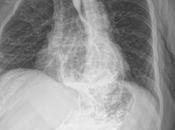

Tele de torax normal

Paciente: Edad: 58 años. Estudio: RX Tórax. Tejidos blandos de morfología y densidad normales.Las estructuras óseas se observan de adecuada morfología y densida... Leer el resto